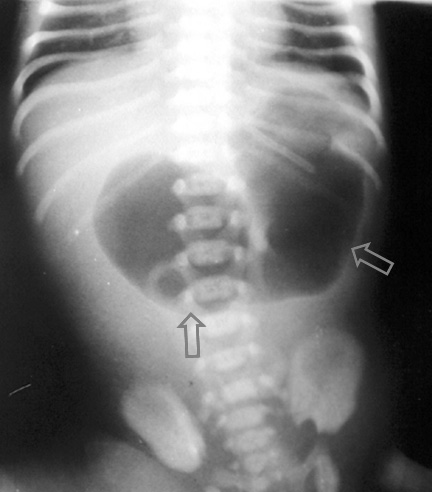

SIGNO DE LA BURBUJA ÚNICA

En el recién nacido, la presencia de la cámara gástrica distendida (flechas) con escasa o nula presencia de gas en el resto de abdomen, indica la existencia de una obstrucción en el tracto de salida gástrico, como atresia gástrica.

Aun cuando el estómago pueda estar distendido en recién nacidos normales, generalmente se aprecia una cierta cantidad de gas distal al estómago, en asas intestinales. Así que su ausencia (burbuja única) favorece el diagnóstico de obstrucción gástrica.